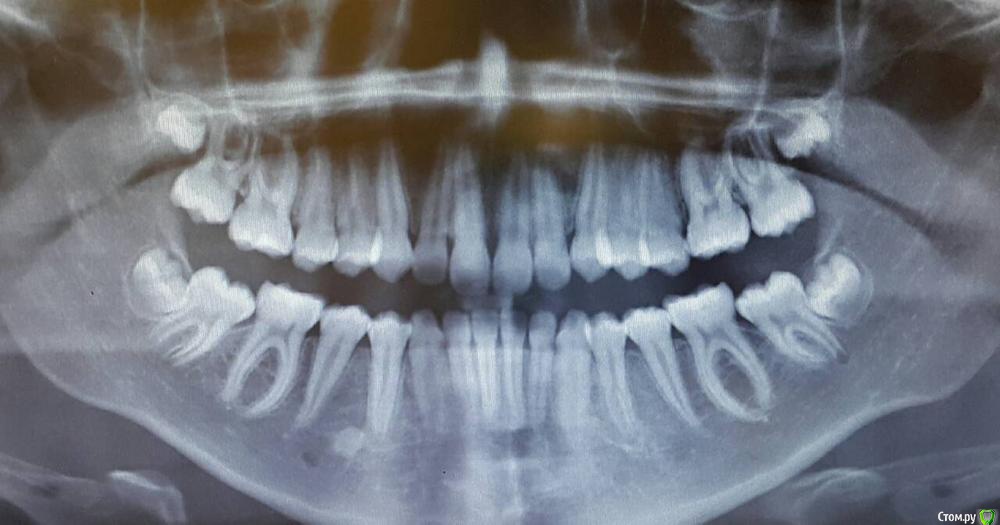

Arbitr Опубликовано 28 октября, 2018 Поделиться Опубликовано 28 октября, 2018 Добрый день!Подскажите, пожалуйста, как лучше, на Ваш взгляд, поступить с 8-ми зубами?Ребенку - 10 лет, Все 4 появились на снимке, расположены, вроде не совсем хорошо.Стоматолог терапевт рекомендует подумать об удалении, что бы избежать проблем в будущем.Удалить сейчас, пока они не заматерели, или ждать, вдруг пронесёт? Ссылка на комментарий

___49___ Опубликовано 29 октября, 2018 Поделиться Опубликовано 29 октября, 2018 Добрый день!Подскажите, пожалуйста, как лучше, на Ваш взгляд, поступить с 8-ми зубами?Ребенку - 10 лет, Все 4 появились на снимке, расположены, вроде не совсем хорошо.Стоматолог терапевт рекомендует подумать об удалении, что бы избежать проблем в будущем.Удалить сейчас, пока они не заматерели, или ждать, вдруг пронДобрый , с нижними точно не пронесет. Перед удалением желательна очная консультация с ортодонтом. 1 Ссылка на комментарий

Brigita Опубликовано 30 октября, 2018 Поделиться Опубликовано 30 октября, 2018 Удалять, нижние точно, чем раньше удалите, тем меньше проблем будет в дальнейшем 2 Ссылка на комментарий